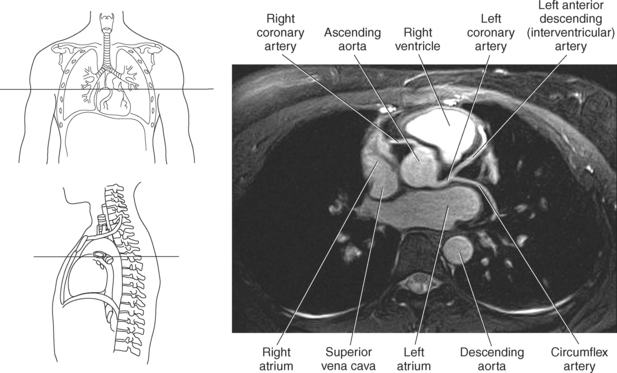

The two main coronary arteries are the first vessels to branch off the ascending aorta (Figures 6.91 and 6.92). The right coronary artery arises from the base or root of the aorta (right aortic sinus) and passes anteriorly between the pulmonary trunk and right atrium to descend in the coronary (atrioventricular) groove. As it reaches the diaphragmatic surface, it gives off a right marginal branch that runs toward the apex of the heart. The right coronary artery then turns to the left and enters the posterior interventricular groove, where it gives off the posterior interventricular branch (posterior descending artery). The posterior interventricular branch continues to descend along the interventricular groove toward the apex, where it anastomoses with the left anterior descending artery of the left coronary artery. The right coronary artery and its branches supply the right atrium, right ventricle, interventricular septum, and the sinoatrial (SA) and atrioventricular (AV) nodes. It also supplies a portion of the left atrium and ventricle (Figures 6.92 through 6.96). The left coronary artery arises from the left aortic sinus and passes to the left between the pulmonary trunk and left atrium to reach the coronary groove (Figures 6.91 and 6.92). Soon after reaching the coronary groove, the left coronary artery divides into the circumflex and left anterior descending (interventricular) arteries. The circumflex artery winds around the left border of the heart to the posterior surface, where it gives off the left marginal artery. The left anterior descending artery (LAD) descends in the anterior interventricular groove toward the apex of the heart, where it reaches the diaphragmatic surface to anastomose with the posterior descending artery. The left coronary artery and its branches supply the interventricular septum, including the AV bundles, and most of the left ventricle and atrium (Figures 6.97 through 6.99).